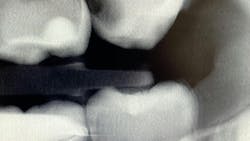

What’s unique about this system is that it uses nanotube technology to capture standard 2D images (figure 2) and gives you the option of taking a tomosynthesis image, which captures multiple images from several angles (figure 3). Images are compiled into a sliced volume and dissected into 0.5 mm or 0.1 mm slices that you can scroll through, rotate, enlarge, measure, and adjust. The system can “un-overlap” many teeth; this is convenient because with regular 2D x-rays, I had to retake the image at different angles and often with little success.

I see more complications and pathologies when using 3D tomosynthesis than I ever did with my old 2D images (figure 4). I can treat more because I can see more bone loss, interproximal caries, fractures, resorptions, abscesses, and more (figure 5).

In fact, twice today I was able to see something with Portray that wasn’t visible in the original 2D x-ray (figure 6). I don’t always take 2D images now, but I do when I think the case is straightforward or the patient has very little dental history. I often end up taking a tomosynthesis image just to be safe. With the 3D image I can scroll from buccal to lingual through the tooth and get much more data (figure 7). The new system has replaced my 2D PAs and bitewings.